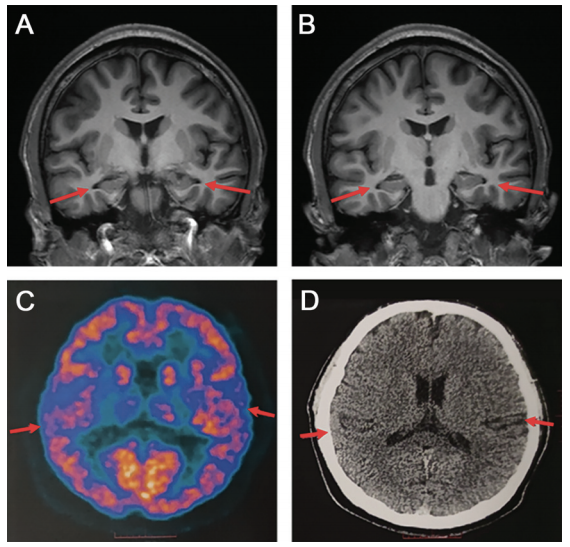

影像学检查:患者脑 MRI 显示双侧海马体轻度萎缩,脑沟和脑裂轻度增宽。脑 PET 成像显示颞叶皮质的双侧低代谢,无明显淀粉样斑块或异常 tau 蛋白沉积。MRA未见异常。(查看阿尔茨海默的辅助检查)。

A:患者顶叶、颞叶皮质、海马结构轻度萎缩,脑沟增大;B:双侧脉络膜稍增宽,颞角未见明显增大;C:双侧颞叶低代谢;D:轻度萎缩